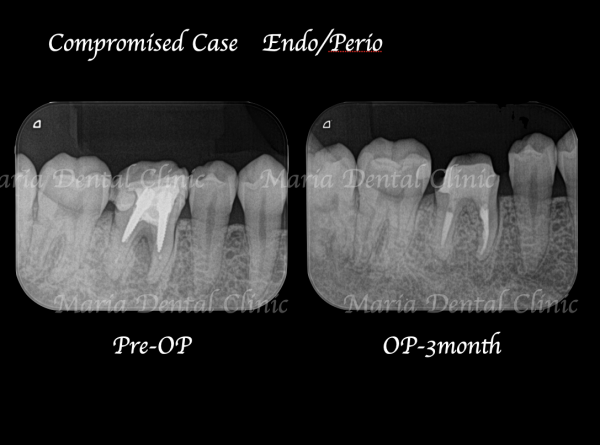

術前の写真を確認すると根の先端から広がる病変の影は歯の股の部分まで大きくなっていることが確認できます(術前写真②)

通法通り根管治療を施したことで歯ぐきの腫脹は改善したものの、分岐部(歯の股の部分)の歯周病に治癒傾向は確認されず(写真1術前)歯周病の治療に移行する判断をしました。

歯周病専門医による組織再生療法を行なった際にはレントゲンで透過像(黒い影)があった歯の股の部分の骨は著しく欠損していました(写真2術中)。骨の欠損部分に組織再生治療を行い、さらに3ヶ月の経過観察を行い生体の治癒を待ちました。

歯周組織再生療法3ヶ月後には分岐部(歯の股の部分)に確認されていた歯周病(術前写真)は完全に治癒していることを確認しました(術後3か月写真)。また同時に、術前に確認できた根尖性歯周炎も綺麗な治癒が確認できたことから最終補綴処置へ移行しました。今後最低2年間は歯肉、根尖周囲組織の治癒経過を患者様にご協力いただき確認していく予定です。